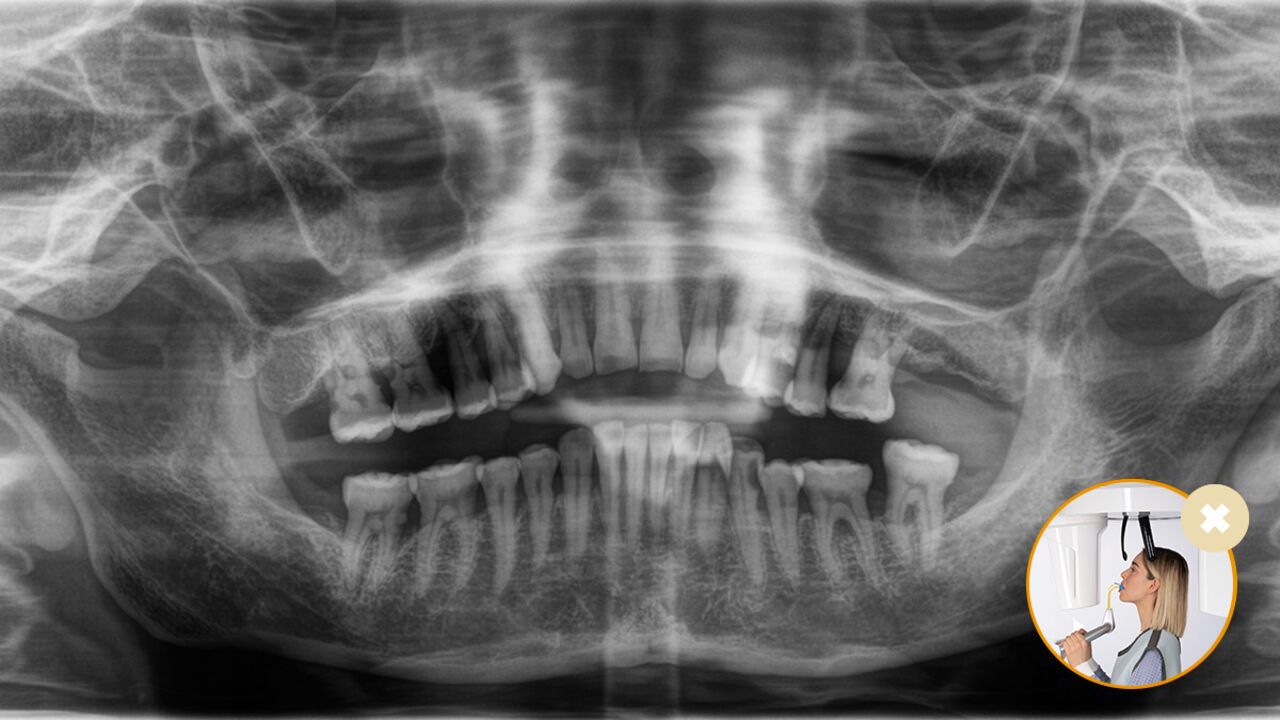

O posicionamento correto do paciente leva à alta qualidade da imagem para apoiar um diagnóstico preciso e facilita e melhora a experiência do paciente.

3. O posicionador automático exclusivo determina automaticamente a inclinação correta da cabeça

7. Compensação automática da coluna vertebral para melhorar a qualidade da imagem panorâmica na região anterior